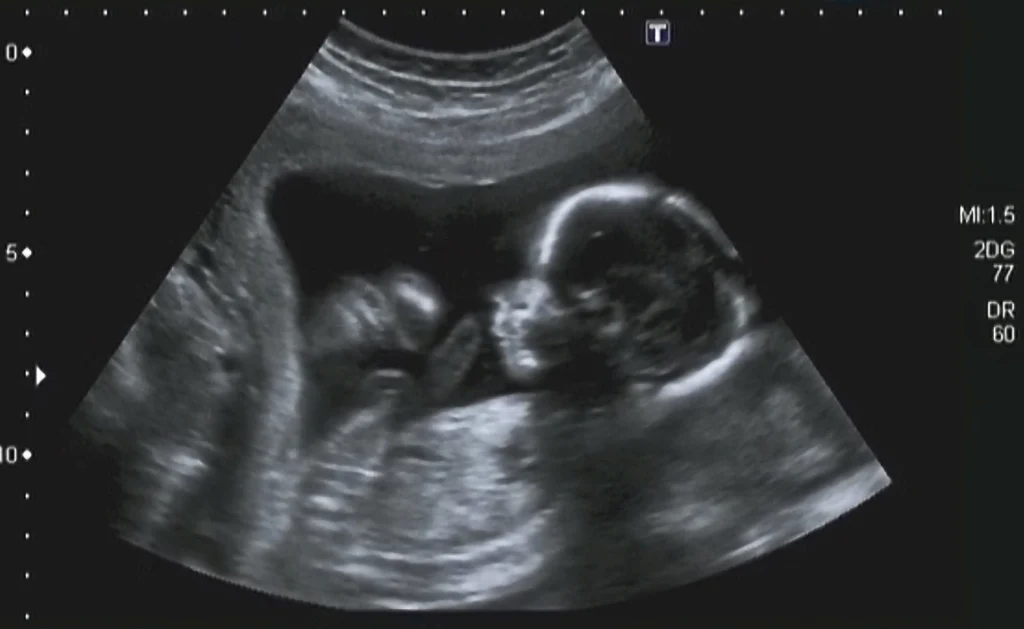

Zespół Edwardsa jest możliwy do wykrycia już na etapie końcówki pierwszego trymetru ciąży. Z pomocą przychodzą badania prenatalne, szczególnie tzw. USG genetyczne, wykonywane około 12. tygodnia ciąży, ukazujące odstępstwa od normy w budowie ciała dziecka. Ewentualne nieprawidłowości, które wykaże USG, są następnie potwierdzane przez badania inwazyjne.